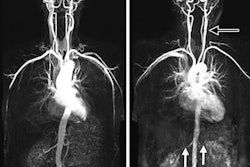

The U.S. Food and Drug Administration (FDA) has issued a letter to healthcare providers warning them that stainless steel neurovascular embolization coils could cause artifacts on MR angiography (MRA) images.

In a March 12 communiqué, the FDA advised users to check for 304V stainless steel in coils, which could cause "larger than expected artifact" in MRA images. The agency said it received information indicating that these coils could be causing artifacts that reduce image quality or result in inappropriate medical decisions.

Digital subtraction angiography (DSA) was previously used to evaluate the patient's condition and view the implanted coil, but healthcare providers have begun using MRA instead due to concerns over radiation from DSA.

If an artifact does occur, the agency recommends that clinicians use DSA to view aneurysms after coiling, rather than MRA. If MRA is the only option, the FDA advises using optimal imaging parameters to minimize any image artifact, including shortened echo times and high readout bandwidth.